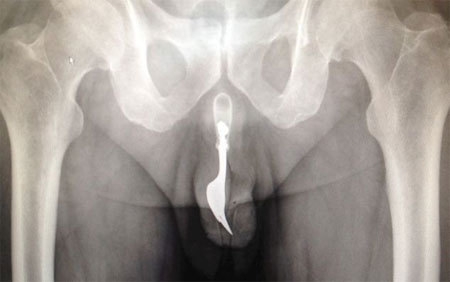

Cụ ông 70 tuổi đã mất tới 12 giờ đồng hồ mới đủ can đảm nhờ cậy bác sĩ sau khi chiếc dĩa mắc kẹt bên trong "cậu nhỏ" của ông. Ảnh: Daily Mail |

Giới truyền thông địa phương đưa tin, cụ ông 70 tuổi đã được đưa vào khoa cấp cứu của Bệnh viện Canberra, Australia trong tình trạng chảy máu dương vật. Ông sau đó thú nhận đã nhét chiếc dĩa vào đường niệu đạo của mình nhằm thủ dâm.

Không may, trò "tự sướng" quái đản diễn ra không như mong đợi và chiếc dĩa bị mắc kẹt bên trong "cậu nhỏ", khiến cụ ông vô cùng đau đớn. Bất chấp điều đó, phải mất tới 12 giờ đồng hồ sau, ông mới có đủ can đảm để nhờ cậy sự can thiệp của các bác sĩ.

Theo báo The International Journal of Surgery, chiếc dĩa cắm ngập sâu bên trong cơ thể bệnh nhân đến mức các bác sĩ ban đầu không biết nguyên nhân khiến ông đau đớn. Tuy nhiên, sau khi được tiết lộ căn nguyên sự việc và xác định được vị trí của "thủ phạm", họ đã tiến hành nhiều thủ thuật trích lấy chiếc dĩa ra ngoài bằng kìm kéo và chất bôi trơn.